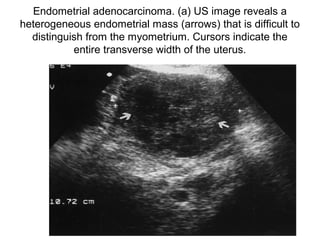

ENDOMETRIAL CARCINOMA

• Occurs mainly in postmenopausal

women

• Most common presenting symptom

abnormal uterine bleeding

Ultrasound features

• vary from endometrial thickening

to an irregular hypoechoic

intracavitatory mass to an enlarged

diffusely infiltrated uterus.

Endometrial adenocarcinoma. (a) US image reveals a

heterogeneous endometrial mass (arrows) that is difficult to

distinguish from the myometrium. Cursors indicate the

entire transverse width of the uterus.